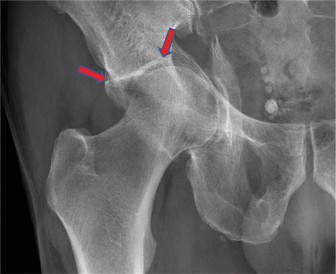

A 52-year-old postmenopausal female presents with progressive hip pain. She points to the pain in “C-clamp” d…